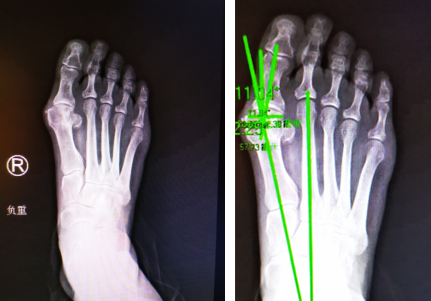

足踝科徐明亮主任接待了她,检查发现许大姐双足均踇趾外翻畸形,与第2趾挤压重叠,关节红肿疼痛,右足更严重,结合相关影像,确诊为后天性双侧踇外翻伴踇囊炎,决定先实施右足踇外翻微创矫正手术。

很快,徐主任为许大姐进行了右足踇外翻截骨矫形内固定+踇内收肌松解术。手术团队采用不到1厘米切口,4毫米进口超声磨锯微创截骨,手术全程无血渗出,近乎完美地修整了右足踇外翻。